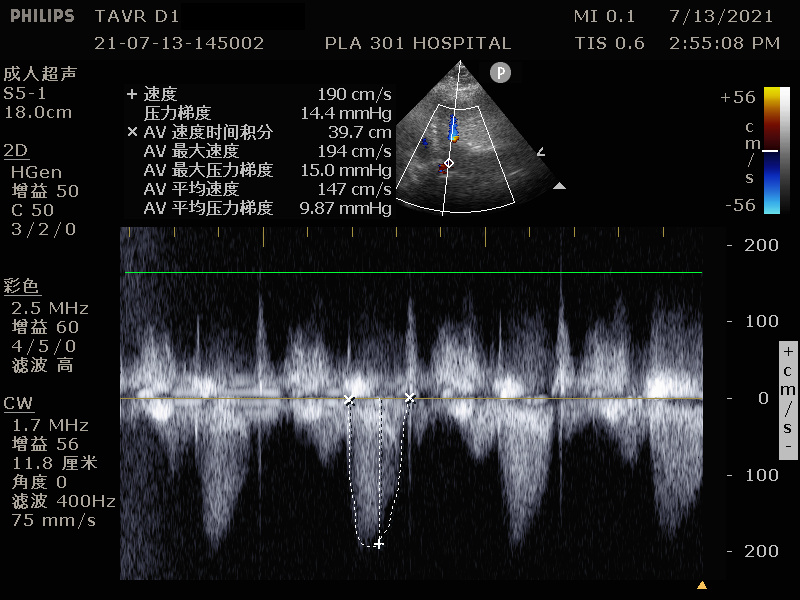

术后患者超声结果:

患者AV前向血流速度降低至1.9m/s,平均跨瓣压差10mmHg,手术效果非常理想。